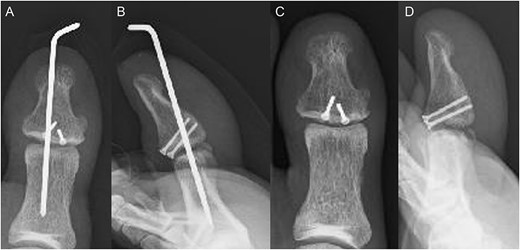

A 54-year-old man injured his right great toe while walking and wearing sandals. He complained of tenderness, swelling, and pain during motion. He could bear weight but could not actively extend the interphalangeal (IP) joint of the hallux. He was referred to our outpatient clinic 3 days after the injury. Physical examination revealed swelling, tenderness, and motion pain, and the patient could not extend the IP joint of the hallux. Plain lateral radiography and computed tomography revealed a displaced avulsion fracture of the dorsal base of the distal phalanx (Fig. 1). Surgery was performed under general anesthesia after informed consent was obtained on posttraumatic day 11. A Y-shaped incision was made at the center of the dorsal IP joint, and the displaced bony fragment was attached to the extensor hallucis longus (EHL). The IP joint was temporarily fixed with a 1.6 mm Kirschner wire, and the fragment was repositioned and fixed with two 1.5 mm cortical screws (APTUS® Hand, Medartis, Basel, Switzerland). A 4-0 FiberWire® (Arthrex, Naples, FL, USA) was fastened as an augmentation proximally to the EHL tendon and distally to the periosteum of the distal phalanx in a figure eight (Fig. 2). Postoperatively, the ankle was externally fixed in dorsiflexion from the leg to the toe, and heel loading was permitted. A total of 4 weeks after surgery, the Kirschner wire was removed to allow active motion of the IP joint of the hallux, and weight bearing was allowed on the hallux 5 weeks postoperatively. Plain radiographs taken 3 months after surgery confirmed bone healing (Fig. 3). A total of 20 months postoperatively, the patient acquired normal function, and the range of motion of the affected IP joint ranged from −3° to 30°, with no difference from the unaffected side (Fig. 4). Skin necrosis or nail deformities were not observed.

Postoperative plain radiographs (A) anterior–posterior view and (B) lateral view show the fragment fixed with two screws and temporarily fixed IP joint with Kirschner wire. Plain radiograph 3 months after surgery (C) anterior–posterior view and (D) lateral view indicates the bone union.